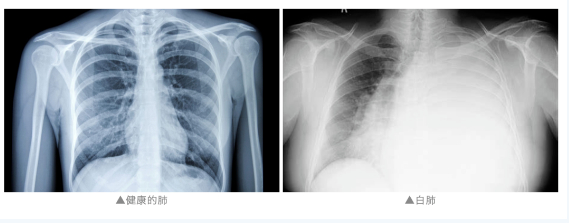

“白肺”是指急性呼吸窘迫综合征

主要发生在重症感染时

双肺弥漫性病变进展迅速